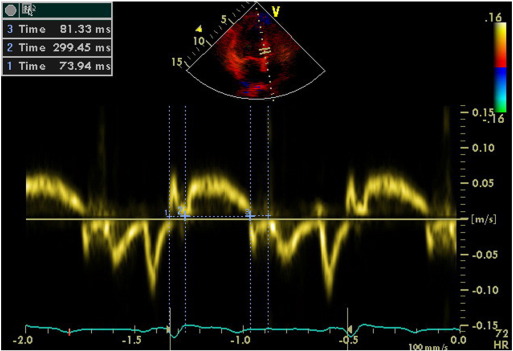

Tissue Doppler Imaging (TDI) permits a quantitative assessment of both global and regional function and timing of myocardial velocities. Pulsed TDI was performed at transducer frequencies of 3.5-4.0 MHz, adjusting spectral Doppler filters until a Nyquist limit of 15-20 cm/s was reached, and using minimal adequate gain. TDI was performed using LV apical 4-chamber imaging and sample volume was subsequently placed on the basal septal (Fig. 1) and basal lateral segment walls in the apical four-chamber view. It is documented that the basal region is associated with the greatest and the most reliable tissue velocity compared with other regions [10]. The imaging angle was adjusted to ensure a parallel alignment of the sampling window with the myocardial segment of interest. Color noise reduction was adjusted, and a color Doppler scanning frame rate of 100 to 140 Hz was used. Myocardial E’ and A’ waves were obtained from LV septal wall, than E/E’ was calculated. Isovolumetric contraction time (IVCT), contraction time (CT), and isovolumetric relaxation time (IVRT) were measured and myocardial performance index (MPI) calculated from the base of septal and lateral walls using the Tei Index which was shown to be valuable in hypertensives [11].

Fig. 1. Evaluation of isovolumetric contraction time, contraction time and isovolumetric relaxation time of the LV septal base by tissue Doppler imaging in a hypertensive patient (MPI = 51). |

We calculated TDI-derived regional MPI using the values of both systolic and diastolic parameters at LV septal base (Fig. 3), then lateral base and found that MPI values were significantly abnormal at both region in group II compared with those in group I and group III (both p < 0.0001, Table 3). However, despite abnormal MPI in both hypertrophied LV walls, septal MPI was more severely impaired compared with that of lateral MPI in group II (p = 0.012). Septal MPI was correlated moderately with septal wall thickness (r = 0.447, p < 0.001, Fig. 4).

Fig. 3. Evaluation of isovolumetric contraction time, contraction time and isovolumetric relaxation time of the LV septal base by tissue Doppler imaging in a hypertensive patient with left ventricular hypertrophy (MPI = 62). |